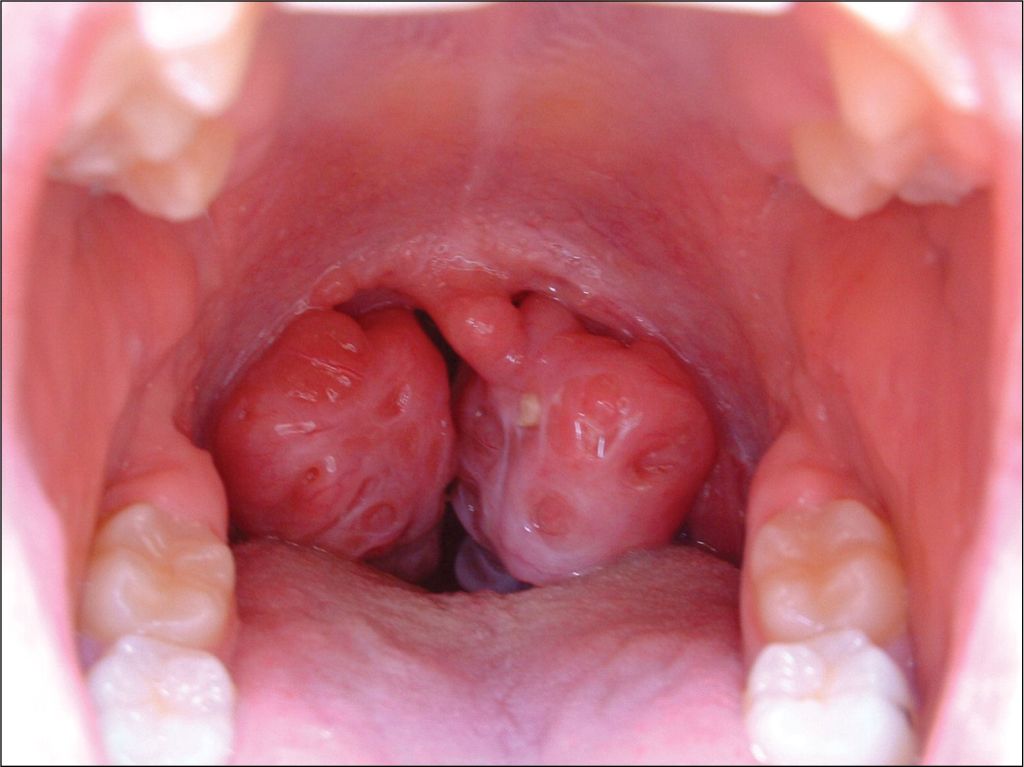

1. Enlarged Tonsils and Adenoid

Research indicates that enlarged tonsils and adenoids are among the leading causes of snoring in children. These structures can obstruct the airway during sleep, leading to snoring and sleep-disordered breathing.

1. Consult an ENT Specialist

A comprehensive evaluation by an ENT specialist can identify anatomical issues like enlarged tonsils or adenoids. Surgical interventions, such as tonsillectomy or adenoidectomy, may be necessary in severe cases.